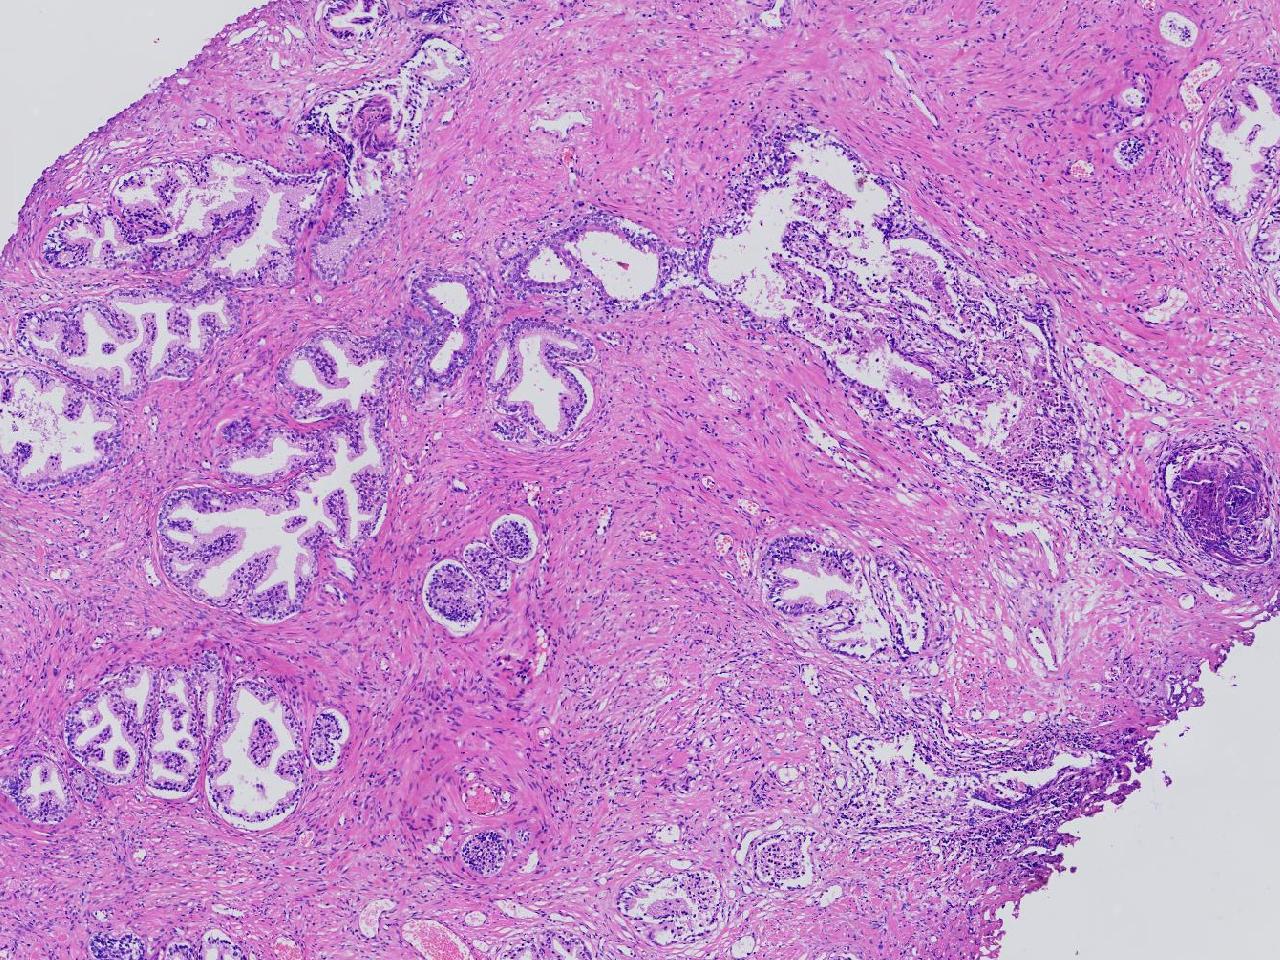

良性前列腺增生?

男,68岁,前列腺电切标本。

前列腺电切标本

灰粉色条索状软组织多块,5X4X3厘米。

前列腺增生。

BPH.